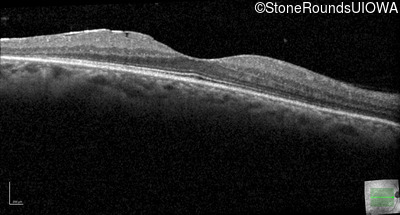

Optical Coherence Tomography - Right - 20/16

Exemplar / OCT Stack